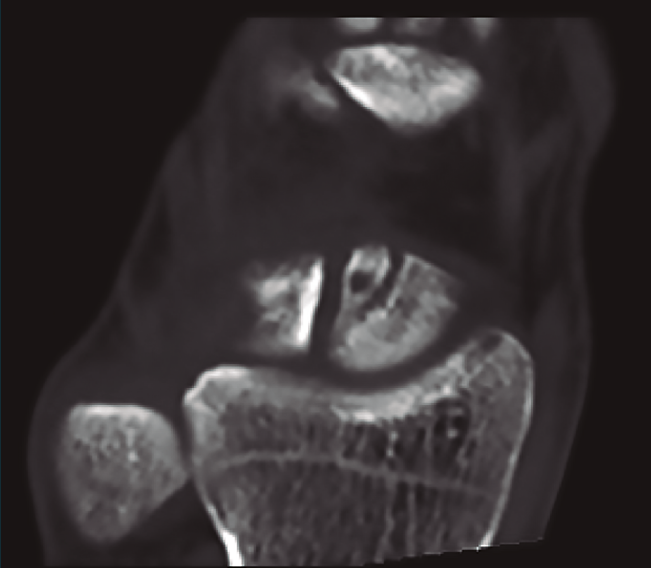

Figura 12. Pequeño fragmento polar superior.

A pesar de todo esto, existen situaciones clínicas específicas que pueden precisar un tratamiento diferente, como pueden ser las fracturas marginales del polo superior del escafoides con preservación del ligamento escafolunar, que pueden tratarse mediante la exéresis del fragmento óseo (Figura 12), o fracturas de pequeño tamaño donde utilizaremos microtornillos no canulados (Figuras 13A y 13B).

Figura 13. Tomografía computarizada donde se evidencia fragmento pequeño y síntesis con 2 microtornillos.